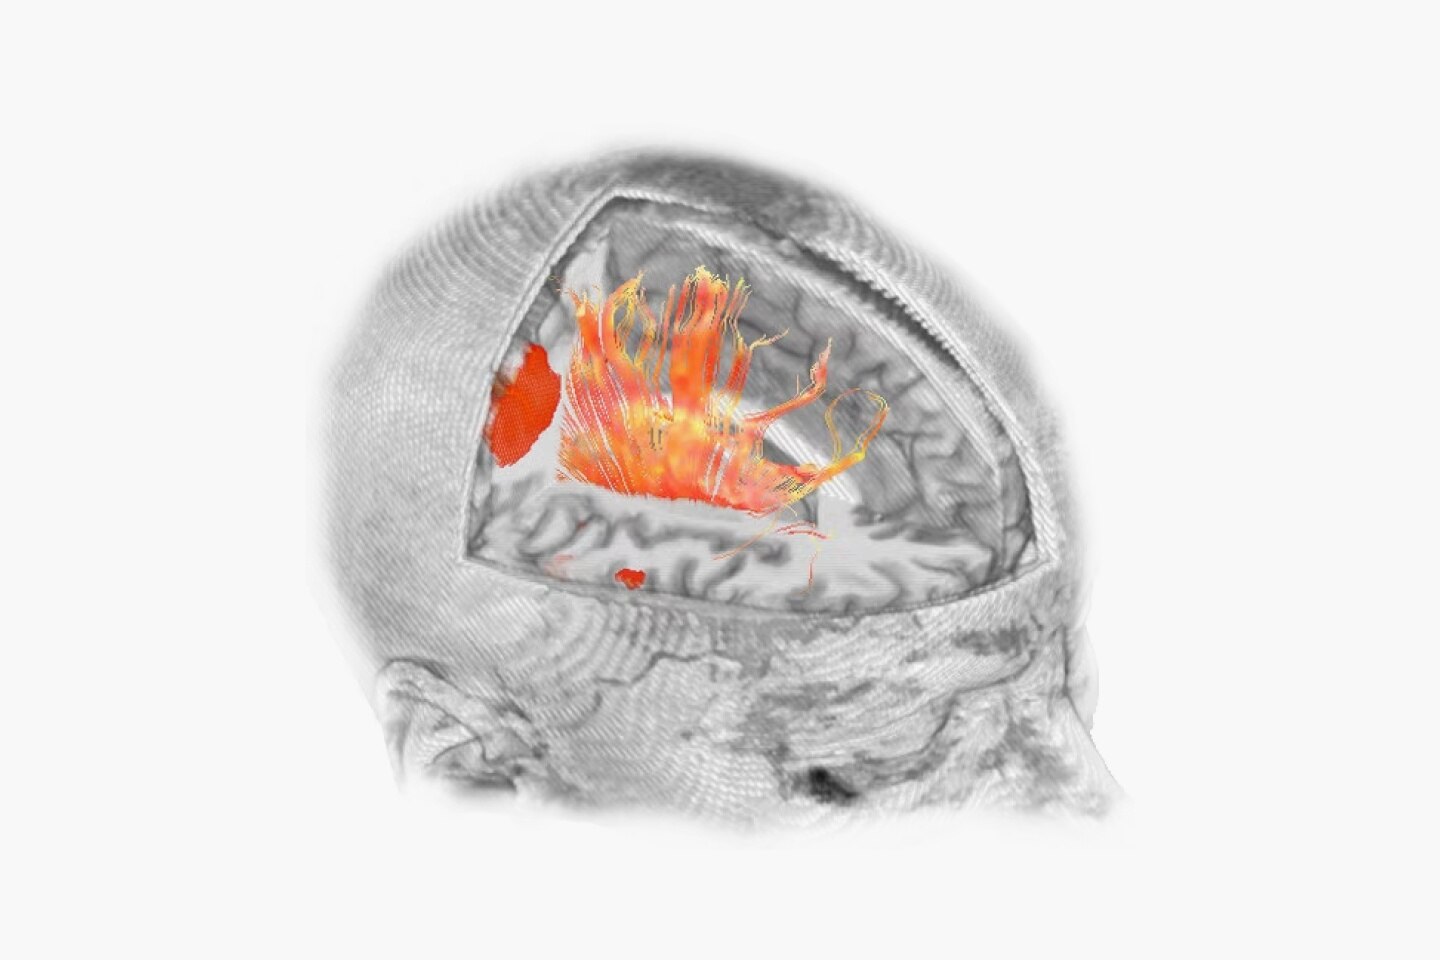

En la RM, los tiempos de adquisición prolongados implican que la adquisición de imágenes se vea comprometida por el movimiento del cuerpo. Hasta ahora. Gracias al aprendizaje profundo, hemos reducido los tiempos de adquisición de minutos a segundos, lo que reduce los artefactos de movimiento y la necesidad de repetir las exploraciones. La aceleración con Sonic DL™ equipa al escáner con la capacidad de igualar la velocidad del cuerpo humano, permitiendo adquisiciones de imágenes que antes no eran posibles.

Construido sobre el éxito revolucionario de AIR™ Recon DL, nuestra primera innovación pionera en la reconstrucción de aprendizaje profundo, Sonic DL™ sigue con audacia sus pasos, avanzando en nuestra misión de revolucionar la RM. El aprendizaje profundo, cuando se aplica a la reducción del tiempo de exploración, convierte los minutos en segundos, lo que ofrece la rapidez de una TC y la calidad de una RM. Es mucho más rápido de lo que permiten las técnicas de aceleración convencionales actuales, lo que ayuda a los radiólogos a realizar diagnósticos precisos desde el principio.

Sonic DL™ permite a los departamentos hacer lo imposible: explorar con precisión a pacientes que antes no se podían explorar de forma eficaz. Ahora, incluso los pacientes enfermos y poco colaboradores pueden someterse a exploraciones en cuestión de segundos, lo que proporciona al personal técnico tiempo libre para realizar el procedimiento con tranquilidad. Al minimizar las posibilidades de movimiento y artefactos que distorsionan las imágenes de exploración, se reduce significativamente la necesidad de volver a realizar exploraciones. Con las exploraciones de un solo latido, los pacientes ya no necesitan contener la respiración, lo que crea una experiencia de exploración más cómoda, tanto para ellos como para el personal técnico que las realiza.